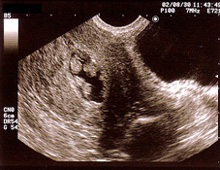

超音波検査(エコー)

卵胞の測定(卵子を含んでいる液体の袋)

卵胞は約20ミリになると排卵します。正確な排卵日と排卵状態を診断します。

- 子宮内膜の厚さの測定

通常、排卵直前の内膜は三層構造で8ミリ以上が望ましい。 - 子宮筋腫、子宮内膜症、卵巣嚢腫などの診断。